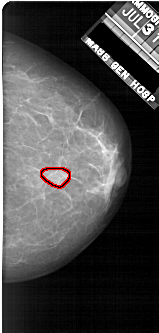

A_1922_1.LEFT_MLO

LEFT_MLO LINES 5371 PIXELS_PER_LINE 2536 BITS_PER_PIXEL 12 RESOLUTION 43.5 NON_OVERLAY

FILE: A_1922_1.RIGHT_MLO.OVERLAY

TOTAL_ABNORMALITIES 1

ABNORMALITY 1

LESION_TYPE MASS SHAPE OVAL MARGINS OBSCURED

ASSESSMENT 3

SUBTLETY 4

PATHOLOGY BENIGN

TOTAL_OUTLINES 1

BOUNDARY